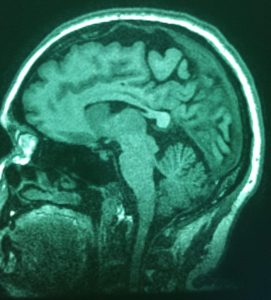

XRAYVSN

“Like the Phoenix rising from the ashes, you can rise above your debt and become financially independent.”

– Xrayvsn